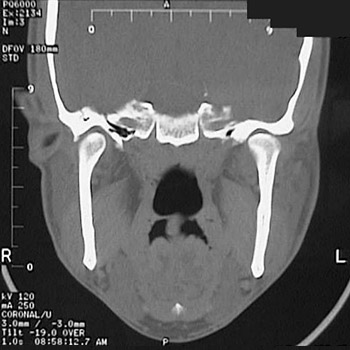

This is a normal sinus CT scan demonstrating the basilar portion of occipital bone and nasopharynx and mandible in the skull.